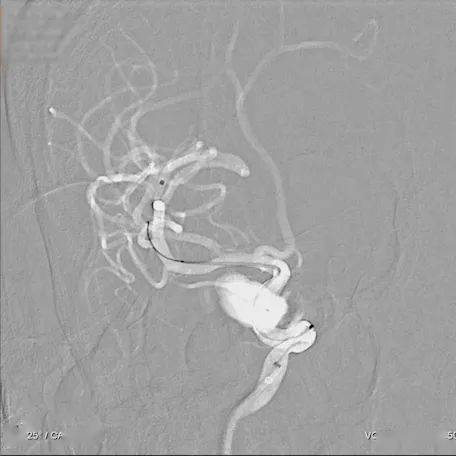

pipeline密网支架血流导向装置治疗大型动脉瘤

图片尺寸2560x1920